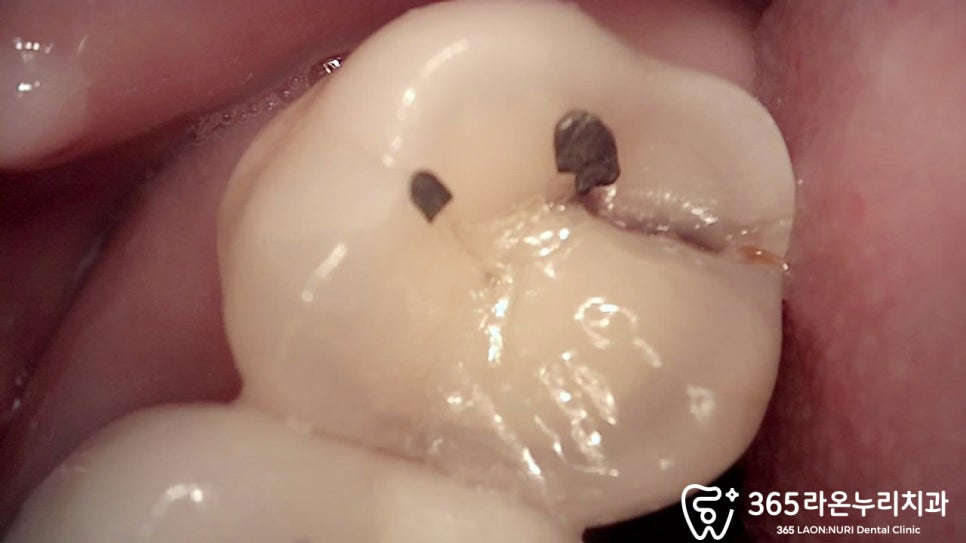

또 불편한 곳을 오산대역 치과 에서

자세하게 살펴보면

깨져 있는 모습을 확인할 수 있습니다.

Qray로 확인했을 때

crack을 더 자세하게 관찰 할 수 있습니다.

crack은 이에 생기는 작은 균열로

쉽게 말해 ‘금이 갔다’라는 소리입니다.

그 어떤 접착제로도

금이 가거나 깨진 이를 붙일 순 없기에

일단 살려보기 위해 임시치아 상태로

지내보면서 지켜보기로 하였습니다.